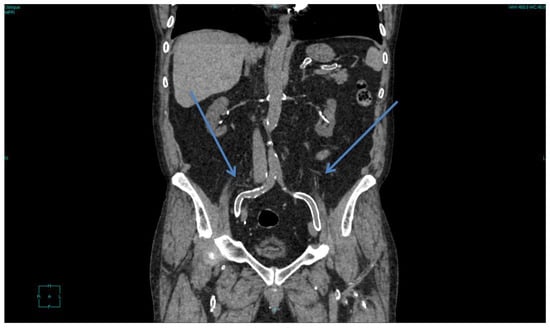

At least in settings where dialysis efficiency has been a key goal in recent decades, the “skeleton man” is now seldom encountered in dialysis wards, except in cases in which diffuse and severe vascular disease is accompanied by a reduction in food intake, often in a context of cognitive impairment in elderly patients [71,72,73,74]. Another exception is patients with a very long dialysis follow-up, whose clinical situation is often dominated by diffuse precocious bone or vascular disease [75,76,77,78,79,80] (Figure 1).

Figure 1.

Diffuse vascular calcifications in a patient with more than 30 years of follow-up on dialysis and after kidney transplantation. Arrows show eggshell calcifications of the iliac axes; scattered calcifications are visible in all other districts.